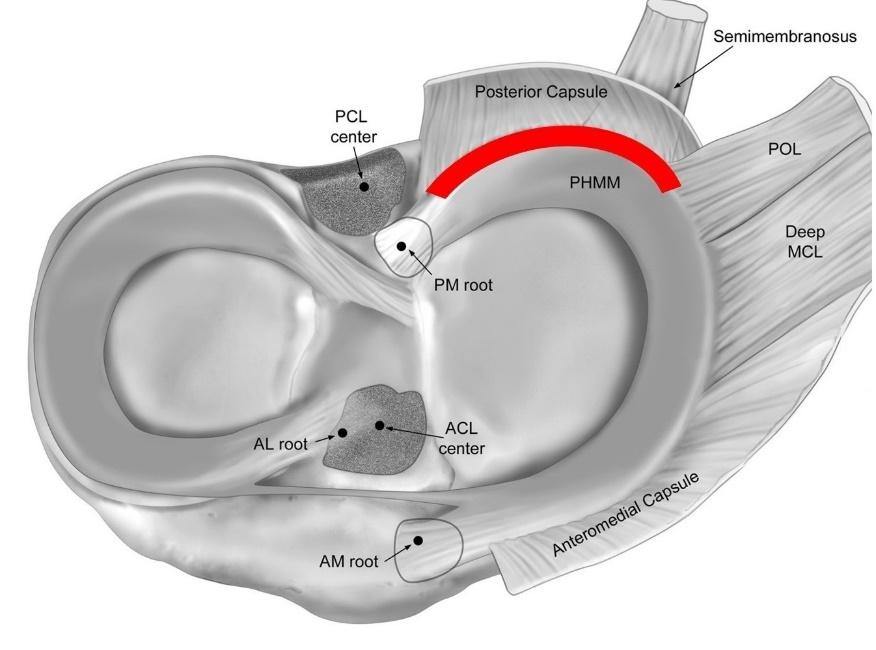

125 Posterior Medial Meniscus Root Tears: Clinical Implications, Surgical Management, and Postoperative Rehabilitation Considerations.

Monson JK, LaPrade RF.